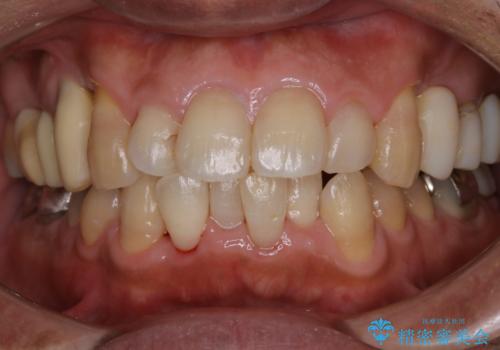

50代男性 1年ぶりにPMTC 前歯をきれいに

- 1年ぶりの来院だが30分コースで前歯だけ綺麗にクリーニングしてほしいとのことでした。

PMTC30分コースで前歯メインにクリーニングを行いました。